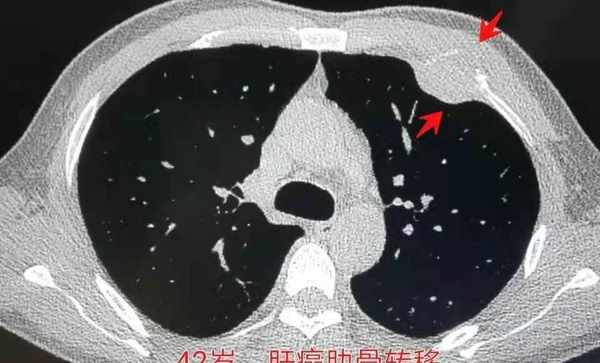

医生检查后发现,大军的肝脏处长出了一个肿瘤,并且已经大面积的扩散,根本无法进行肿瘤切除手术,只能保守治疗。两个月后,大军离世了。

肝脏早期受损一般是不会出现疼痛现象的,若是感觉到疼痛,就需要留心自己是否时患上了脂肪肝、肝硬化或是肝病的肝部疾病了,一定尽早去医院做个肝 CT,查明病因。